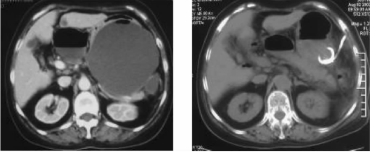

125I放射性粒子治疗肺癌,3个月后肿瘤消失,仅见粒子影像